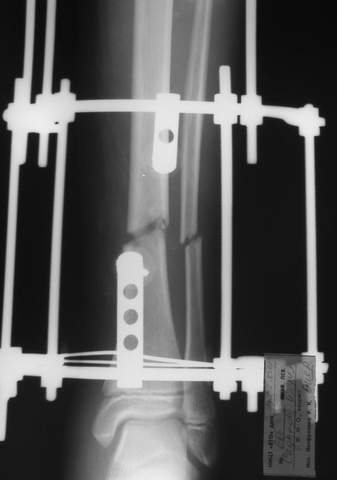

В аттачте № 3 - один из примеров полукольцевого аппарат...

Это уже я баловался.

Итог? Работы больше (по времени и

интраоп "подгонке"), срастается также, а особого преимущества по сравнению с

"чиста" кольцевым (вес, удобство ношения и пр.) - я, по крайней мере,

не нашел.

Теперь не балуюсь.

МТ мы используем, конечно, не только на голени. В прилагаемом примере у парня при поступлении была наружная ротация 40 гр. и "полумертвый" коленный сустав. Можно был бы, конечно, до конца использовать полную компоновку. Но для того он и есть метод выбора.